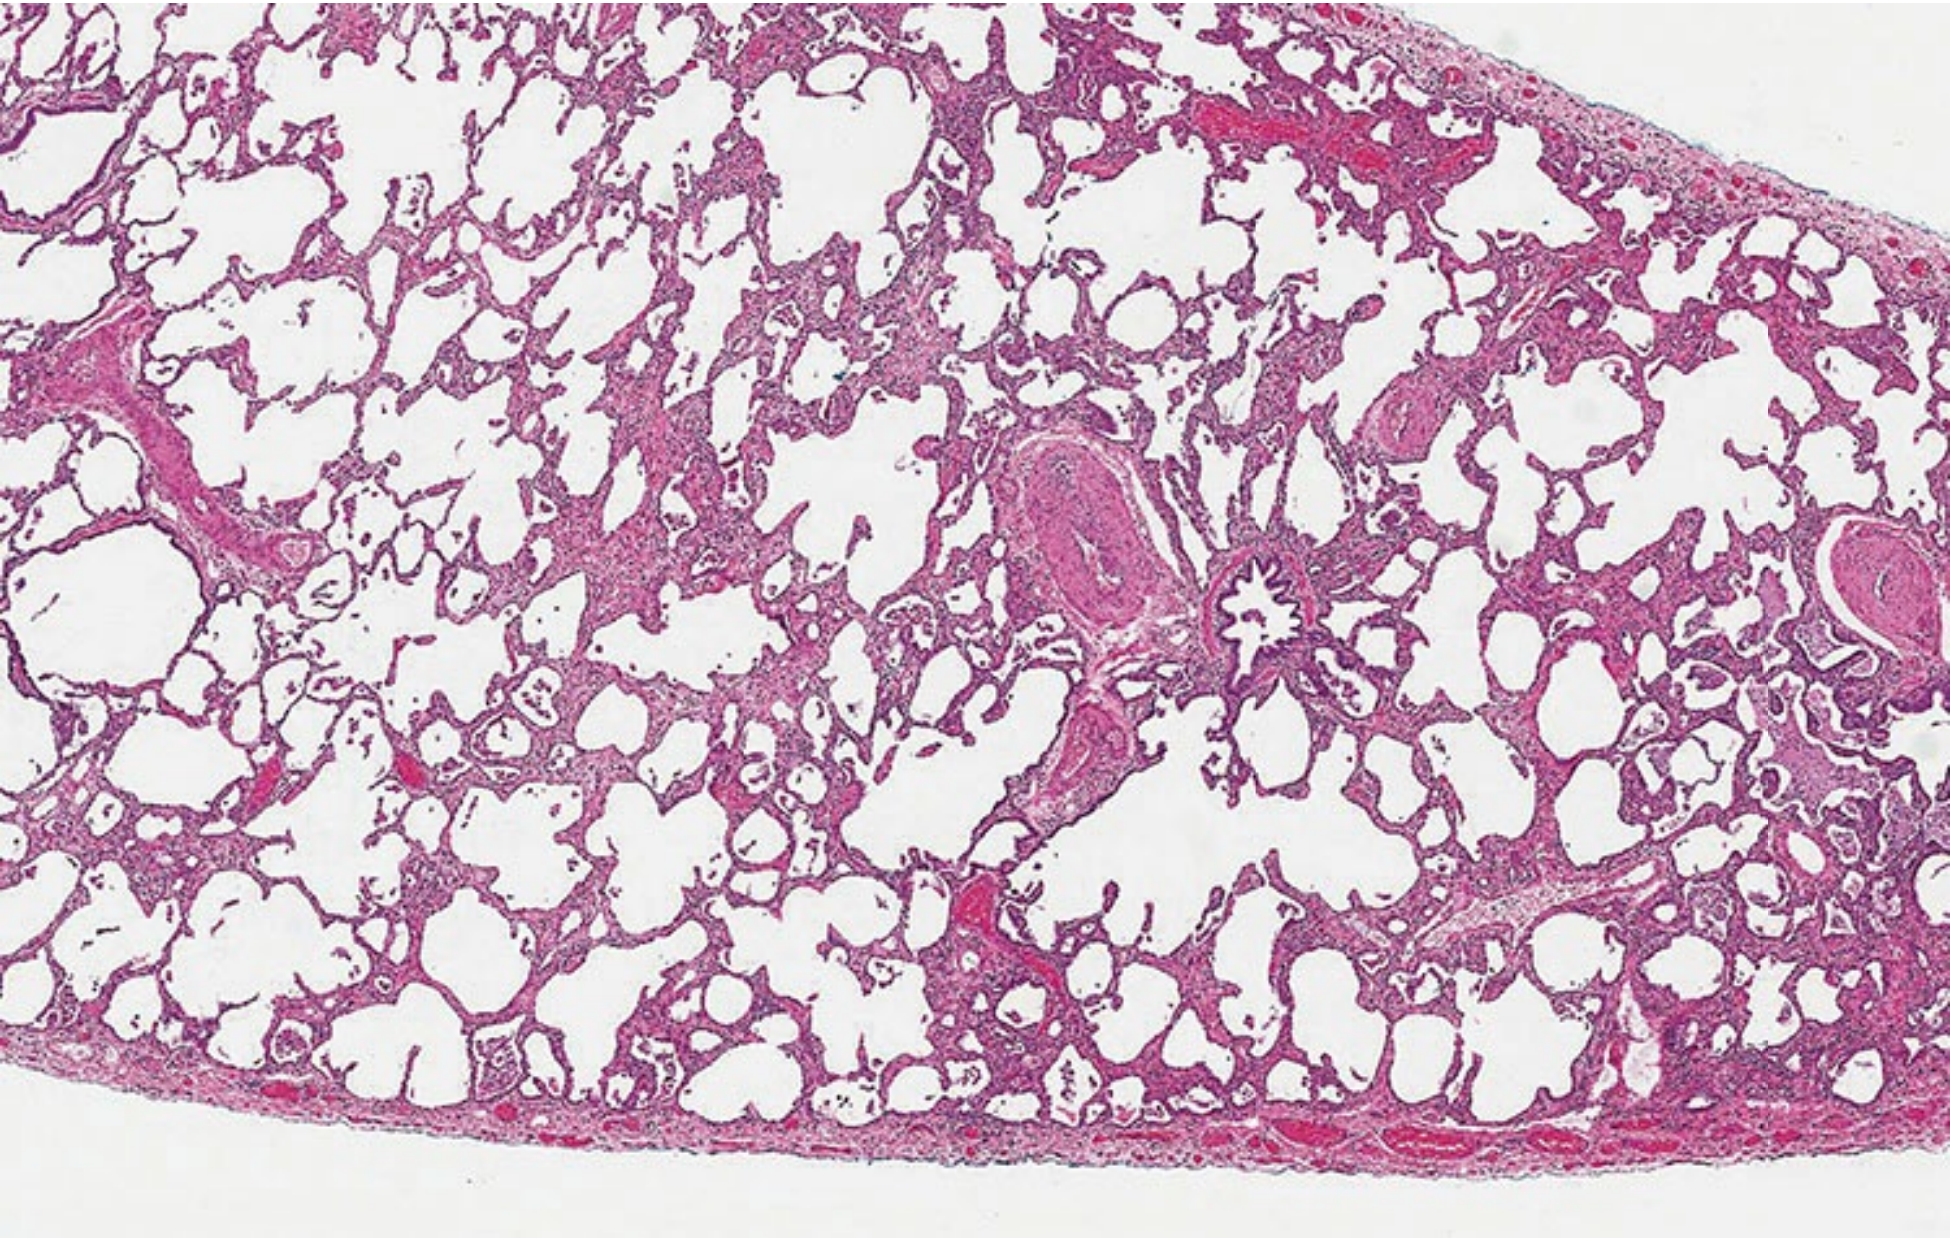

00dafb2b850d4a2ee56c89ae9e94e2fd.png非特异性间质性肺炎的病理表现。

由于肺纤维化,肺泡壁呈弥漫性增厚, 但几乎没有肺结构扭曲。